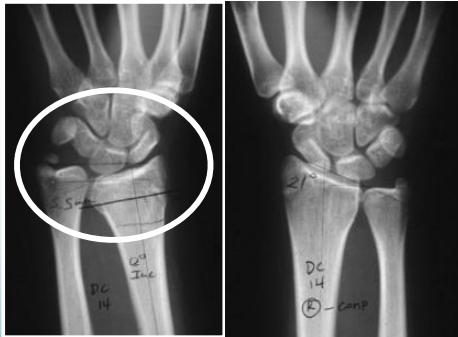

Injured and uninjured wrists after premature physeal closure

Injury films